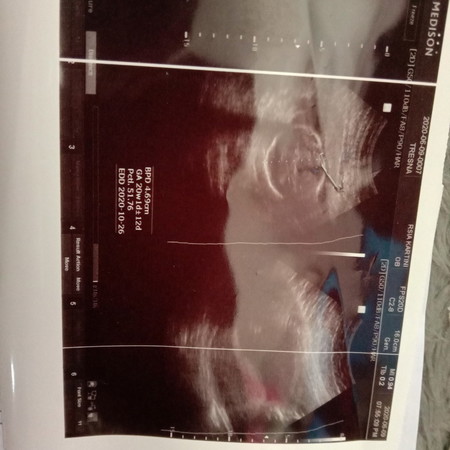

kondisi kesehatan janin

Bagaimana kondisi janin saya sekarang